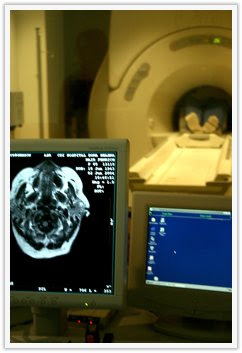

Two is the new six for me, in regards to children. I tried three this weekend and ended up in the hospital. Here’s the quick version: My oldest sister, Angela, is in town and brought her little munchkin too. I thought it would be a brilliant idea if I tended her this morning so she could sleep in. My sister was a little hesitant having me tend all three, but I was SURE that it would be no problem. Skip forward an hour later. Vienna is sleeping. Ethan and Alyvia were happily playing while I was showering. Then they weren’t happily playing. So I jumped out of the shower (dripping wet) and picked both of them up (since when did I think I was She-Ra?). Somewhere between the master bedroom and bathroom, I slipped and wasn’t able to balance myself with the two toddlers being almost half my weight. I hit my head on the tile. Apparently, very hard. I began to black out, but I kept focusing on two things: 1) I don’t want the kids to be in a room with running water and 2) I don’t want emergency personnel to see me naked. So I got up to the spinning room. The kids were fine, but blood was all over and the sounds of the fall had woken my sister from her sleep and she came screaming downstairs. Luckily, she is a doctor… granted a tooth doctor, but still a doctor. She knew just what to do. Stitches, CT scan, and a concussion later, I am completely fine. Good as new. The only hitch is that I can’t go to sleep for twelve more hours. Hence, me writing on the blog. No need to ask how I am. I am completely fine. I felt so bad for myself that I had two ice cream cones today and ended up buying myself a new coat online. I will post a photo soon. There rarely is something that I love more than a great coat. I have quite a collection of coats. It’s a pity I don’t live in Minnesota or Russia.

Two is the new six for me, in regards to children. I tried three this weekend and ended up in the hospital. Here’s the quick version: My oldest sister, Angela, is in town and brought her little munchkin too. I thought it would be a brilliant idea if I tended her this morning so she could sleep in. My sister was a little hesitant having me tend all three, but I was SURE that it would be no problem. Skip forward an hour later. Vienna is sleeping. Ethan and Alyvia were happily playing while I was showering. Then they weren’t happily playing. So I jumped out of the shower (dripping wet) and picked both of them up (since when did I think I was She-Ra?). Somewhere between the master bedroom and bathroom, I slipped and wasn’t able to balance myself with the two toddlers being almost half my weight. I hit my head on the tile. Apparently, very hard. I began to black out, but I kept focusing on two things: 1) I don’t want the kids to be in a room with running water and 2) I don’t want emergency personnel to see me naked. So I got up to the spinning room. The kids were fine, but blood was all over and the sounds of the fall had woken my sister from her sleep and she came screaming downstairs. Luckily, she is a doctor… granted a tooth doctor, but still a doctor. She knew just what to do. Stitches, CT scan, and a concussion later, I am completely fine. Good as new. The only hitch is that I can’t go to sleep for twelve more hours. Hence, me writing on the blog. No need to ask how I am. I am completely fine. I felt so bad for myself that I had two ice cream cones today and ended up buying myself a new coat online. I will post a photo soon. There rarely is something that I love more than a great coat. I have quite a collection of coats. It’s a pity I don’t live in Minnesota or Russia.